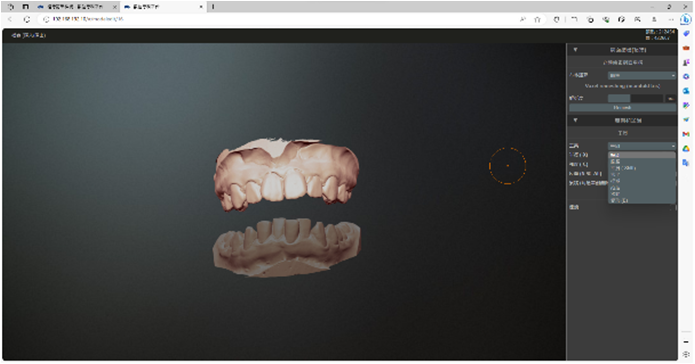

Occlusal line angle and maximum cusp position of upper and lower teeth

- Patent notice for tooth arrangement and production method of Maximal Intercuspation Position (MIP) occlusal line angle and maximum cusp position of upper and lower teeth

- The concept of Maximal Intercuspation Position (MIP) is the basis of the field of dentistry and orthodontics. However, it is challenging to pinpoint exactly when these ideas were first proposed because they have been developed and refined over a long period of time.

- occlusal line angle

- The occlusal angle line refers to the angle formed by the occlusal plane, which is essentially the imaginary surface where the upper and lower teeth come into contact during biting and chewing. This concept has been around for a long time and is critical to understanding bite mechanics, jaw alignment, and orthodontic treatment planning.

- Maximal Intercuspation Position (MIP) of the upper and lower teeth

MIP, also commonly referred to as "center bite," is the position where the upper and lower teeth come together in an optimal or "maximum" bite. This is an important concept in diagnosing and treating malocclusion as well as restorative dentistry.

- MIP, also commonly referred to as "center bite," is the position where the upper and lower teeth come together in an optimal or "maximum" bite. This is an important concept in diagnosing and treating malocclusion as well as restorative dentistry.

- History background

- Both concepts date back to early dental literature but have been refined extensively with the advent of modern dentistry in the 20th century.

- Although it is difficult to attribute the origin of these ideas to a specific date or individual, they have been an integral part of dental science for a considerable period of time and continue to evolve with ongoing research and clinical experience. The use of X-rays, 3D imaging, oral scans and computer modeling can also help to understand these concepts in more detail.

- According to the development of this concept, the use of digitally built occlusal retainers (positioners) on the articulator to control the growth and occlusal alignment of teeth can be accomplished based on the occlusal angle line.

矯正牙科病患齒列不正的問題

位置 Maximal Intercuspation Position(MIP)

- line angle與建立上下牙齒的最大尖窩位置 Maximal Intercuspation Position(MIP) ,根據這個方法申請專利,成為首個製造出咬合與排牙兼具的COMiP牙套。

- 正式收專利公告通知,以咬合線為基準的排牙法,是一種齒列橋正牙套及其製造方法,該齒列橋正牙套可用於進行牙科矯正。該製造方法需取得上 顎下顎的齒位構造圖,並透過牙科軟體讀取 、顯示該齒位構造圖,將上顎牙齒的多個窩凹連成 一上咬合線的弧線,將下顎牙齒的多 個齒尖連成一下咬合線的弧線, 再透過該上下咬合線而生成一矯正弧線,進而生成尖窩對應的上顎矯正槽位及下顎矯正槽位,再以之生成該齒列橋正牙套的上下顎對應件,再用以矯正牙科病患齒列不正的問題 。

關鍵字:咬合角度線 occlusal line angle、最大牙尖交錯位置

- 關鍵字:咬合角度線 occlusal line angle、最大牙尖交錯位置、MIP、矯正、牙齒病史、咬合力學、中心咬合、咬合不正。

- The concepts of the occlusal line angle and maximal intercuspation position (MIP) are fundamental in the field of dentistry and orthodontics. However, it's challenging to pinpoint exactly when these ideas were first proposed, as they have been developed and refined over a long period of time.

- Occlusal Line Angle

- The occlusal line angle refers to the angle formed by the occlusal plane, which is essentially the imaginary surface along which the upper and lower teeth make contact during biting and chewing. This concept has been around for a long time and is essential for understanding bite mechanics, jaw alignment, and orthodontic treatment planning.

MIP、矯正、牙齒病史、咬合力學、中心咬合、咬合不正。

- Maximal Intercuspation Position (MIP)

- MIP, also commonly referred to as "centric occlusion," is the position where the upper and lower teeth fit together in the most ideal or "maximum" interlocking way. It's a crucial concept for diagnosing and treating malocclusions, as well as for prosthetic dentistry.

Keywords: Occlusal Line Angle, 最大尖窩位置 Maximal Intercuspation Position(MIP) , MIP, orthodontics, dental history, bite mechanics, centric occlusion, malocclusions. 。

- Historical Context

- Both concepts have roots going back to early dental literature but have been extensively refined with the advent of modern dentistry in the 20th century. The use of X-rays, 3D imaging, oral scan,and computer modeling has also helped in understanding these concepts in greater detail.

- While it's difficult to attribute the origination of these ideas to a specific date or individual, they have been integral parts of dental science for quite some time and continue to evolve with ongoing research and clinical experience.

- We have officially received a patent notice. The tooth arrangement method based on the bite line is a dental bridge brace and its manufacturing method. The dental bridge brace can be used for dental correction. This manufacturing method requires obtaining the tooth structure diagram of the upper and lower jaws, reading and displaying the tooth structure diagram through dental software, connecting the multiple fossa of the upper jaw teeth into an arc of the upper occlusal line, and connecting the multiple cusps of the lower jaw teeth. The cusp tips are connected to form an arc of the bite line, and then a correction arc is generated through the upper and lower bite lines, and then the upper jaw correction slot and the mandibular correction slot corresponding to the cusp fossa are generated, and then the dentition bridge is generated. Orthodontic braces are matching parts for the upper and lower jaws, and are used to correct the problem of dental misalignment in dental patients.